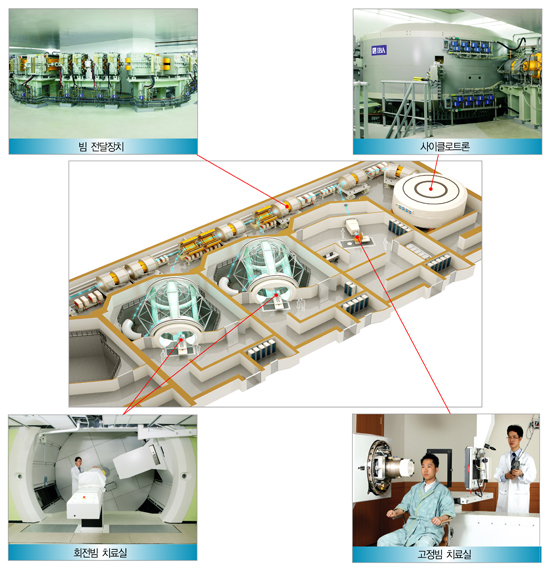

양성자 치료시설